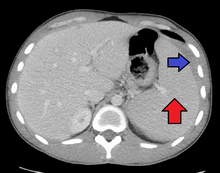

Spleen enlargement is common in the second and third weeks, although this may not be apparent on physical examination. Rarely the spleen may rupture. There may also be some enlargement of the liver.[20] Jaundice occurs only occasionally.[12][21]

A few studies on infectious mononucleosis have been conducted in a primary care environment, the best of which studied 700 patients, of which 15 were found to have mononucleosis upon a heterophile antibody test. More useful in a diagnostic sense are the signs and symptoms themselves. The presence of an enlarged spleen, and swollen posterior cervical, axillary, and inguinal lymph nodes are the most useful to suspect a diagnosis of infectious mononucleosis. On the other hand, the absence of swollen cervical lymph nodes and fatigue are the most useful to dismiss the idea of infectious mononucleosis as the correct diagnosis. The insensitivity of the physical examination in detecting an enlarged spleen means it should not be used as evidence against infectious mononucleosis.[20]

Splenomegaly is a common symptom of infectious mononucleosis and health care providers may consider using abdominal ultrasonography to get insight into the enlargement of a person's spleen.[50] However, because spleen size varies greatly, ultrasonography is not a valid technique for assessing spleen enlargement and should not be used in typical circumstances or to make routine decisions about fitness for playing sports.[50]